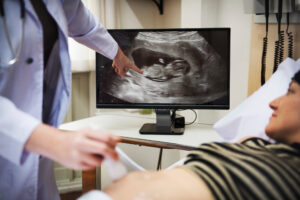

Introduction Pregnancy scans, also called prenatal ultrasounds, are important medical tests during pregnancy. These scans use sound waves to create images of your baby inside